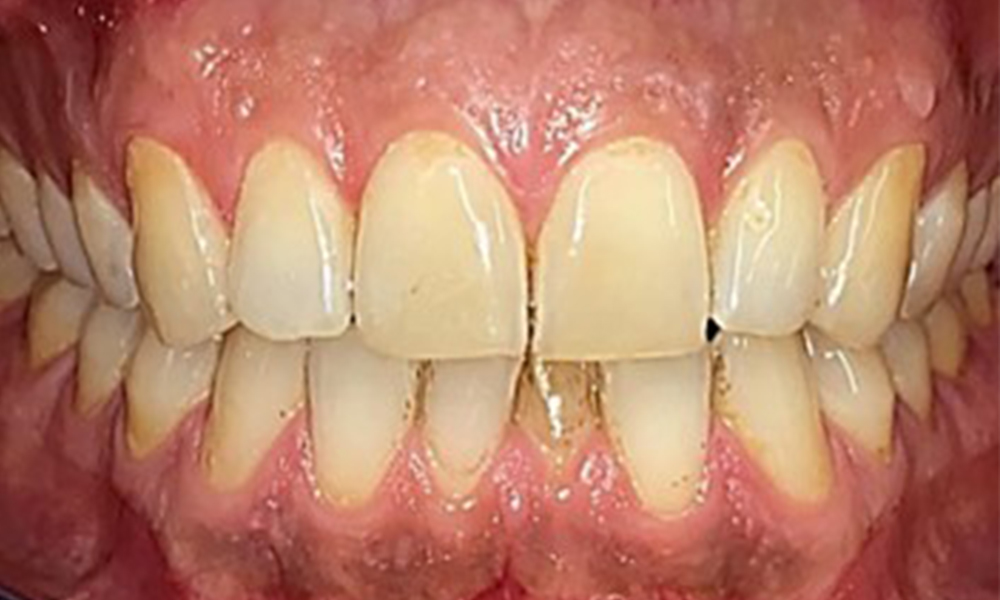

Frontalansicht

Abb. 2 Frontalansicht, © Dr. R. Krapf

Extraoral sind keine pathologischen Befunde festzustellen, intraoral zeigen sich bei der Frontalansicht im Bereich der keratinisierten Gingiva und am Übergang zur beweglichen Schleimhaut bräunlicheVerfärbungen (Abb. 2), welche auf den Nikotingenuss zurückzuführen sind. Am Gaumenbereich zeigen sich insbesondere im Bereich Oberkiefermolaren palatinal weißliche Schleimhautveränderungen, die ein Hinweis auf einen erhöhten Verhornungsgrad sind und ebenso auf den Nikotingenuss zurückzuführen sind. Die Zunge ist mit einem weiß-bräunlichen abwischbaren Belag versehen.